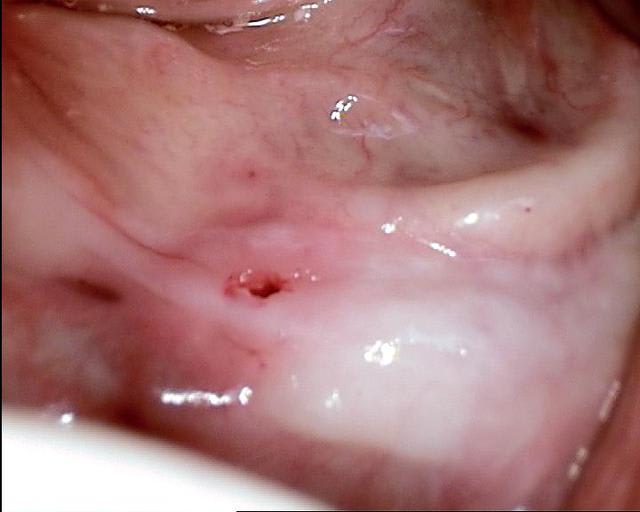

Les deux premières photos montrent le cas d´une jeune femme ( qui malheureusement s est fait retiré toutes les dents à l´étranger....).Ce cas a pu être terminé deux semaines après l´implantation.

Les deux dernières photos montrent le même cas deux ans plus tard.